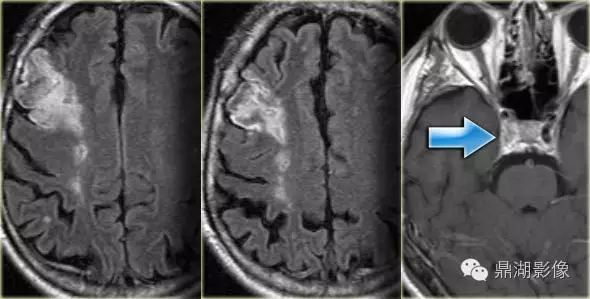

大脑中动脉梗塞(同时累及深穿支及皮层支)

a345d755a0bb4289fe7ce0f3edc883ef.jpg

大脑后动脉梗塞(大脑后动脉供应丘脑、枕叶、中脑)

bd3aa55525aad65019d45b62f9cc5624.jpg

分水岭梗塞(外分水岭和内分水岭)

ce41b2b33f038df087e0d5b30c3599e4.jpg